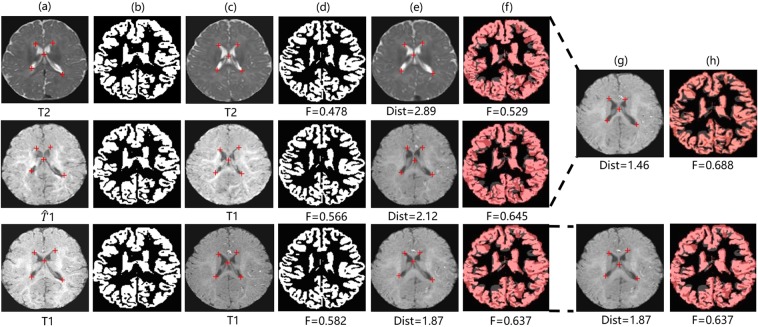

After the weighted fusion process, we find that registrations with translated images show better performance than those with real data by achieving higher Dice, e.g. 0.657 (T2 + ) vs. 0.635 (T2) and 0.534 (T1 + -Flair) vs. 0.517 (T1), both got p-value < 0.0001 on t-test. We also observe that the Dist is greatly shortening (e.g. 2.216 (T2-Flair + ) vs. 3.417(T2-Flair), p-value < 0.0001 on t-test) compared to registrations without adding cross-modality information. In many cases, our method even advances the upper bound both in Dist and Dice. These results are reasonable because our translated images are realistic enough, as well as the real data itself with high contrast for brain structure leads to lower registration errors. Figure 8 visualizes samples of the registration results of our methods. More details can be found there.

Figure 8.

Samples of registration results of our method: (a) Fixed image, (b) Ground truth segmentation label of fixed image, (c) Moving image, (d) Ground truth segmentation label of moving image, (e) Warped image (moving image warped by the best traditional registration algorithm (ANTs), (f) Warped ground truth segmentation label of moving image, (g) Fused image, (h) Segmentation prediction of fused image. The pink, dark red, grey areas in (f) denote true regions, false regions, and missing regions respectively. The red crosses denote landmarks in the fixed and moving images.